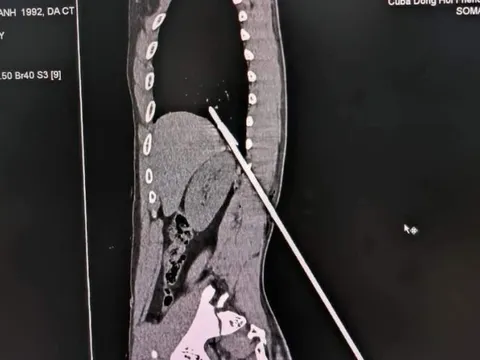

Cứu người đàn ông bị mũi tên bằng thép đâm xuyên lưng lên phổi

Trong lúc lặn bắn cá dưới biển, người đàn ông bị mũi tên bằng thép đâm từ lưng vào lồng ngực gây rách nhu mô phổi, xuyên 2 thùy phổi.